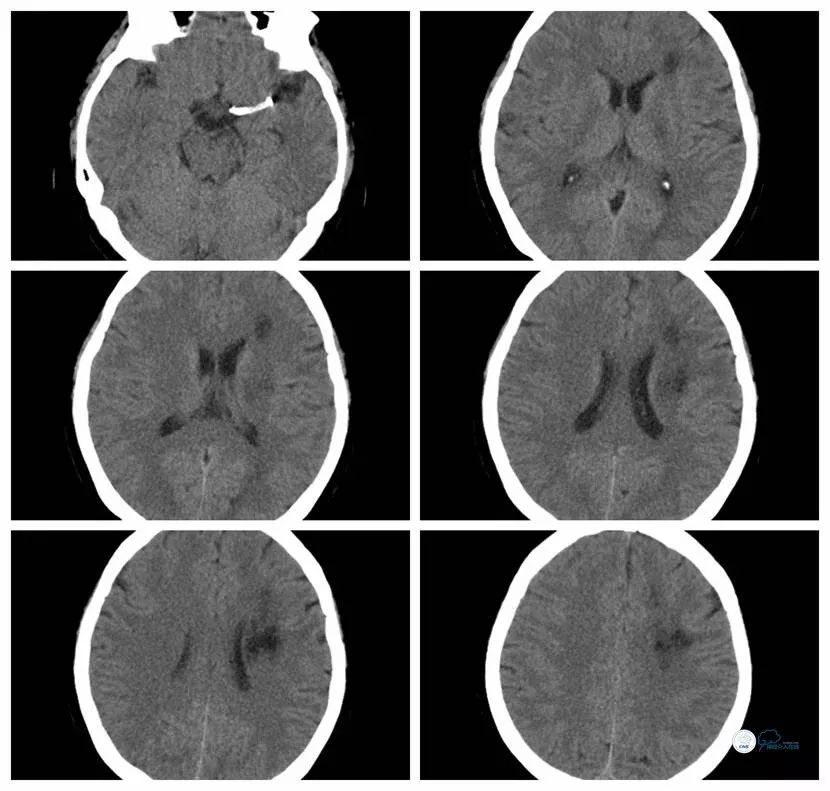

CT(2018-3-30):左侧脑室旁多发脑梗死,梗死面积较前增大(图3)。

图3